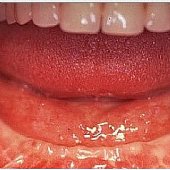

• Die Lachinie der fertigen festsitzenden Versorgung mit Keramikbrücke.

• Die Lachlinie der fertigen festsitzenden Versorgung.

Die Lachinie der fertigen festsitzenden Versorgung mit Keramikbrücke.